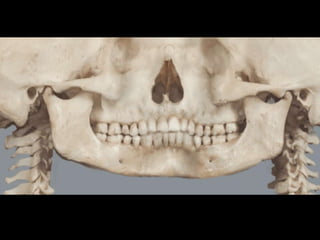

Interpretacion radiográfica

3.

• Las imagenes

son llamadas radio opacas. • Las imagenes son llamadas radio lúcidas.